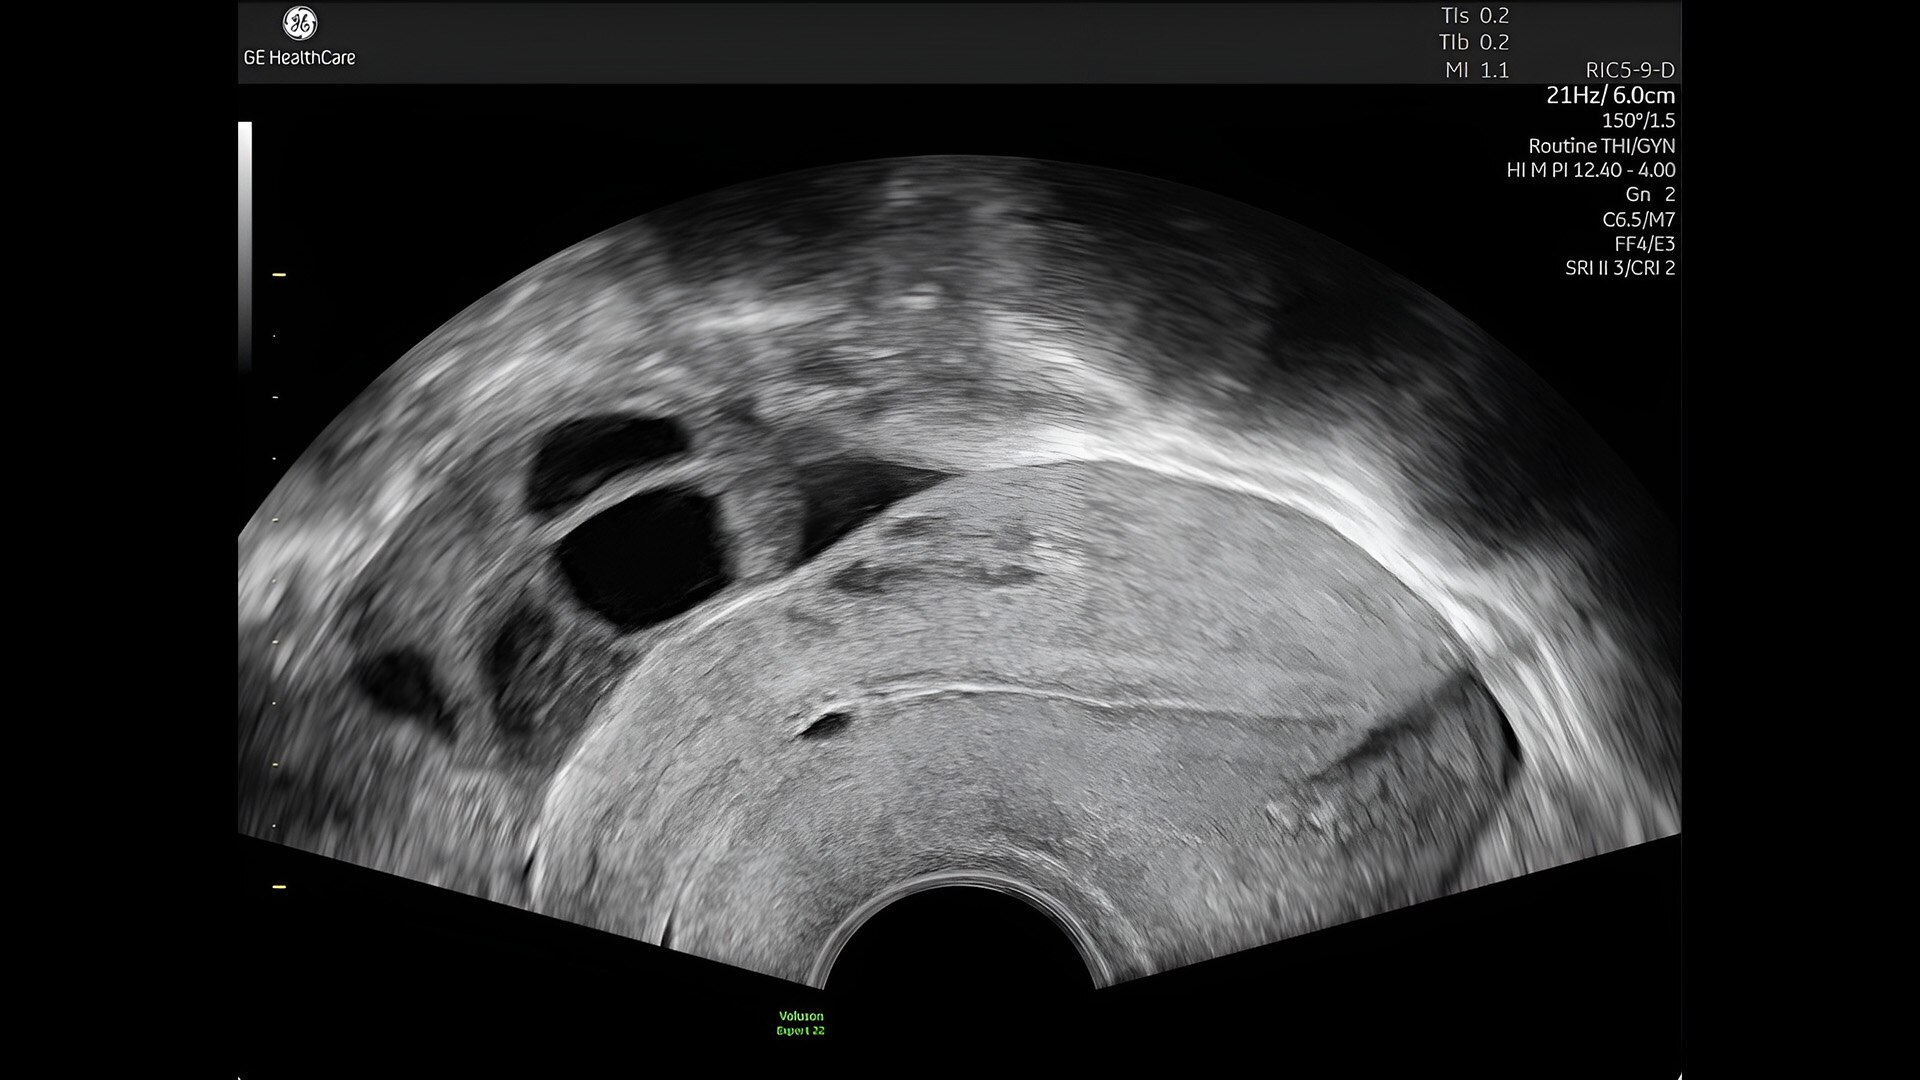

First trimester exams

Perform detailed exams with high-resolution for early insights to fetal health